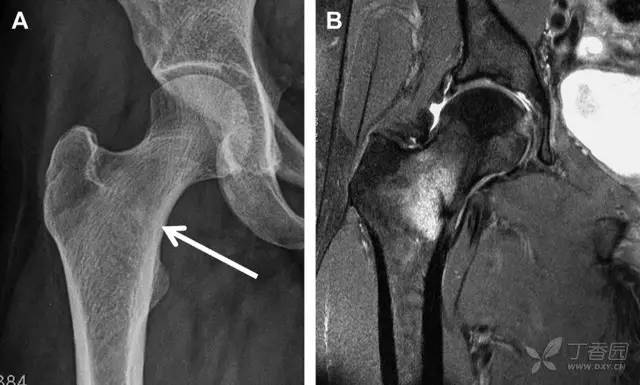

另一种易漏诊的骨折是非典型股骨骨折,这种骨折与长期服用双膦酸盐相关,常发生在使用双膦酸盐 3 年以上的患者。前驱症状表现为腹股沟痛或大腿痛的患者中,60%~70% 被错误地认为由腰背痛或髋关节炎引起。

这种骨折的一个典型表现为火山口状骨膜隆起及一横行透亮带。值得注意的是,超过 50% 的患者表现为股骨干完全骨折。由于 50%~60% 的患者会累及双侧,所以一旦一侧下肢确诊,需行对侧下肢检查。

图 10 老年患者长期服用双磷酸盐引起的骨折。A 髋部正位片,箭头所示,股骨外侧皮质存在横行透亮带。B 后续的股骨 X 线片示局灶性骨膜反应,以及此类骨折的特征性表现-火山口状骨膜隆起(箭头)。C MRI 冠状位 STIR 序列扫描示相应骨折平面的骨髓水肿表现